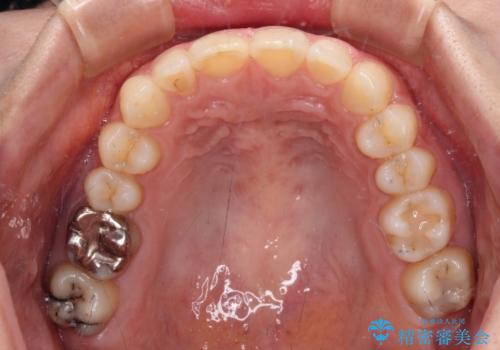

上下ともにデコボコの程度は著しいものではなく、インビザラインで十分に対応可能な歯列不正でした。

後戻りによりスペースができてしまうことを避ける目的で、IPR(歯と歯の間を削る)を極力用いない矯正治療を行うこととしました。